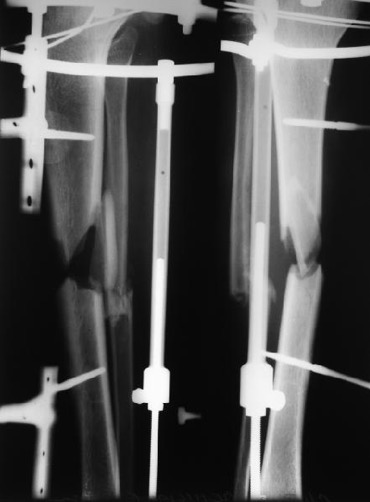

>  При интрамедуллярном остеосинтезе, конечно же, нужна максимальная

> конгруэнтность (параллельность) контактирующих поверхностей.

Совсем необязательно. Это при аппаратной фиксации, чтобы она не была

бесконечной, надо обеспечить максимальную площадь контакта, или делать

что-то дополнительное. Да и если фиксировать пластиной. А когда в диафизе

находится его эндопротез - достаточно сращения на ограниченном участке.